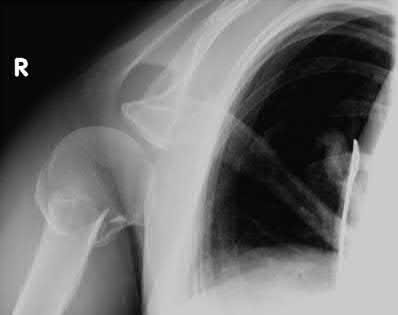

A 62-year-old right-hand-dominant school teacher sustains a mechanical fall at home and presents with right shoulder pain. Plain

radiographs of the right shoulder are pictured in Figures A and B. The patient asks you what she can expect in terms of recovery following this injury. Which of the following is the most appropriate statement?

This patient has a minimally displaced (1-part) proximal humerus fracture involving the humeral neck and greater tuberosity. This injury pattern is most commonly managed nonoperatively with the majority of patients returning to their baseline functional status by 1 year.

Proximal humerus fractures (PHF) can be classified by number of parts (Neer classification), with a part defined as a fracture fragment displaced > 1cm (> 5mm for greater tuberosity) or angulated > 45°. One-part PHF comprise ~80% of all PHF and are treated nonoperatively with a sling and early range of motion (ROM).

Figures A and B are the AP and axillary radiographs of the right shoulder, respectively, demonstrating a 1-part PHF involving the humeral neck and greater tuberosity.